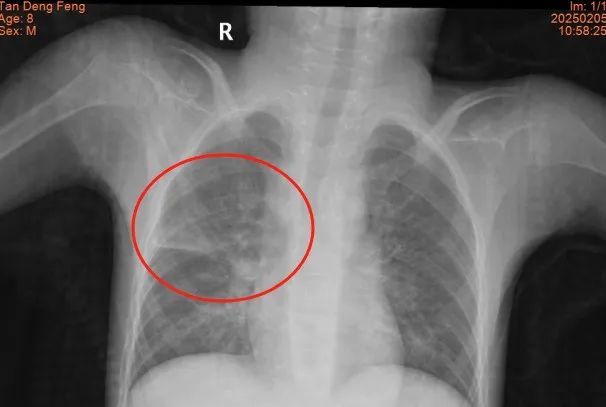

患兒小小,患有腦癱與藥物難治性癲癇,重度營養不良,7歲體重僅10公斤,因長期臥床導致肺部感染并發肺膿腫,入院時情況極為復雜,胸部CT顯示肺膿腫、肺炎合并胸腔積液,高熱不退、呼吸困難,驚厥頻發,治療難度極大,家屬幾近絕望,甚至動過放棄治療的念頭。

接診后,我院兒科團隊第一時間組織呼吸與危重癥醫學科、藥學部等多學科專家會診,全面評估患兒病情后,制定了以抗感染、控制驚厥發作為核心,輔以營養支持和康復治療的個性化治療方案。治療過程中,團隊查閱了大量國內外文獻,結合患兒的具體情況,創新性地采用了一系列治療手段,包括輔助排痰和肺部物理治療等,逐步改善了患兒的癥狀。經過40余天的全力救治,患兒的感染得到有效控制,體溫恢復正常,呼吸功能顯著改善,肺部感染及膿腫完全吸收,最終順利出院。出院當天,患兒家屬激動地表示:“是醫護人員的堅持和專業治療給了孩子第二次生命!”